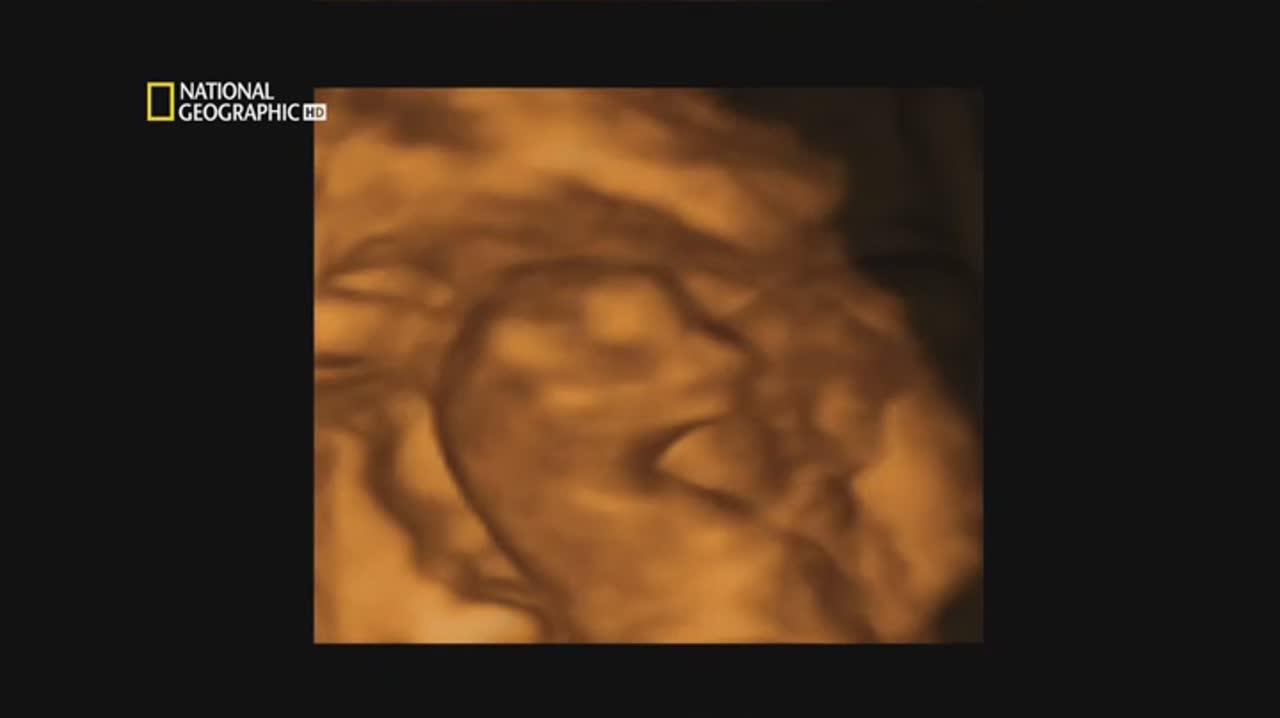

Но близнецы могут и обмануть наши ожидания. Новейшие открытия генетики доказывают, что однояйцевые близнецы не настолько идентичны, как мы думали. С помощью последнего слова науки, четырехмерного ултразвукового исследования, реалистических визуальных эффектов и техники микросъемки нам откроется скрытый от глаз мир эмбрионов близнецов...